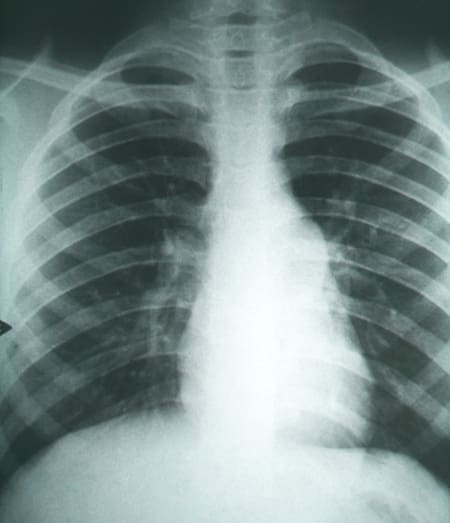

Fibrosis pulmonar secundarias a la coccidioidomicosis.. Foto: Wikipedia.